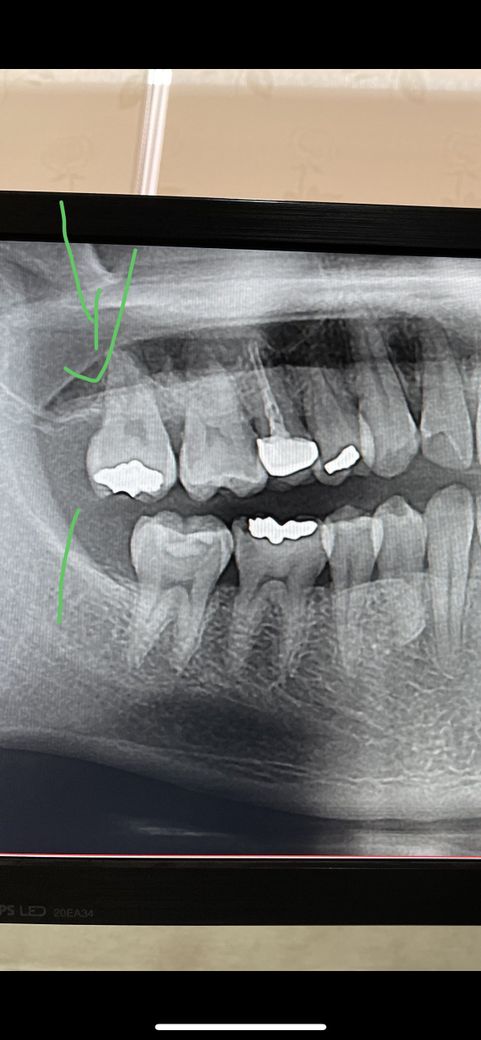

인레이 안에 2차 충치가 생겻을 확률이 높나요???

오른쪽 상악 맨끝치아 17번치아에요

예전에 햇던 치아가 신경치료를 하지 않는 치아이며 안쪽으로 2차 충치가 생겻을 가능성이 잇습니다. 또 골드인레이를 하셧다면 치아에 금이가서 증상이 나타날수도 잇습니다

사진으로봐서는 특별히 이상이 있어보이진 않습니다.

정확한것은 임상적으로 직접 보면서 검사를 해봐야 알 수 있을것같습니다.

인레이가 오래되어 틈이 벌어지거나 2차충치가 생겼거나, 눈에 잘 보이지 않는 크랙이 있을 가능성도 있습니다.